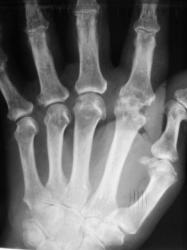

Катенёв Валенти... Дата публикации 03.07.2009, 23:53 Пациент направлен в рентгеновский кабинет "для рентгенографии кистей" терапевтом с диагнозом "Ревматоидный артрит". Произведены рентгенограммы. Ваше мнение коллеги? Сб, 04/07/2009 - 00:59 #1 Петрович Не на сайте Был на сайте: 7 лет 2 месяцев назад Зарегистрирован: 22.03.2009 - 01:13 Публикации: 3908 Для полноценной диагностики "Ревматоидного артрита" маловато представлено костей запястья. А из того, что представлено видна Подагра. Или нет? Неоднозначно всё Сб, 04/07/2009 - 12:12 #2 Ермолаев Не на сайте Был на сайте: 8 лет 10 месяцев назад Зарегистрирован: 07.02.2009 - 16:33 Публикации: 670 Соглашусь с мнением Петровича! Больше похоже на подагрический артрит. dok Вс, 05/07/2009 - 01:12 #3 OPEXOB Не на сайте Был на сайте: 9 лет 11 месяцев назад Зарегистрирован: 26.07.2008 - 10:02 Публикации: 280 Господа, мнения разделились. Поясните, кто что видит, а не окончательный диагноз. Подагра? где тофусы, "пробойники". Вс, 05/07/2009 - 12:31 #4 Ермолаев Не на сайте Был на сайте: 8 лет 10 месяцев назад Зарегистрирован: 07.02.2009 - 16:33 Публикации: 670 Коллега Орехов! Мнения, как раз и не разделились, а сошлись в одном - подагра. dok Вс, 05/07/2009 - 15:50 #5 alexey.krasnov Не на сайте Был на сайте: 10 лет 3 месяцев назад Зарегистрирован: 19.05.2009 - 10:52 Публикации: 30 Абсолютно согласен с Др. Ермолаевым и остальными. Bis Dat Qui Cito Dat

Для полноценной диагностики "Ревматоидного артрита" маловато представлено костей запястья. А из того, что представлено видна Подагра. Или нет?

Подагра? где тофусы, "пробойники".